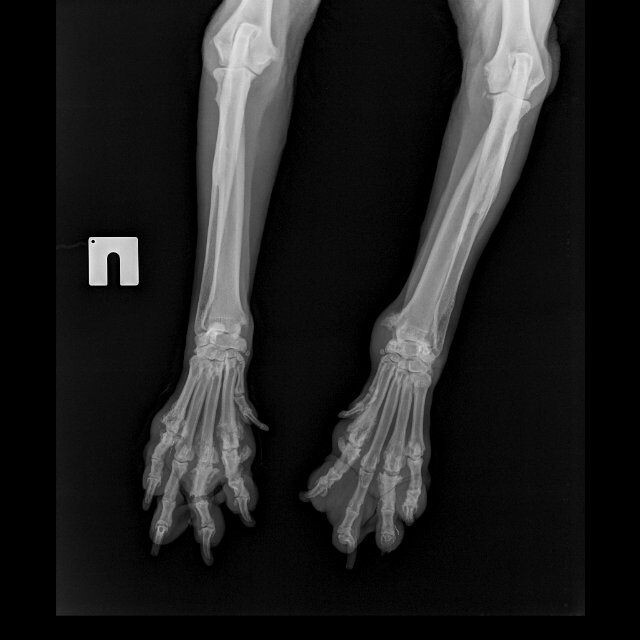

В короткий учебный курс «ОРТОПЕДИЕЧСКАЯ СТРИЖКА КОГТЕЙ» входит видеоурок — практикум по стрижке когтей. Елена ТИМКИНА объясняет нюансы строения когтей на примере собак разных пород и возрастов, делает стрижку. Делится лайфхаками и секретами, показывает инструменты, учит определять причину хромоты собаки, лечить покраснение шерсти и многое другое. В курс входят две подробные лекции с научным обоснованием стрижки и полезной теорией.

- Физиология собаки, строение лапы.